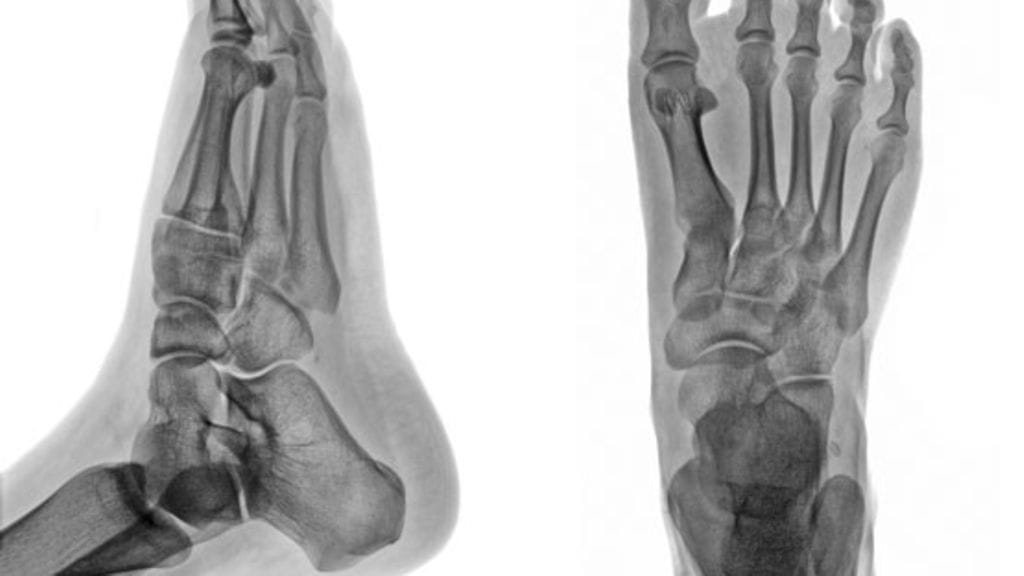

Yksityisellä puolella Kristiinan kantapäästä löydettiin magneettikuvauksissa hiusmurtuma.

Lääkäri päätti mitata Kristiinan luuntiheyden. Sen perusteella hänellä todettiin maaliskuussa 2008 osteoporoosi eli luukato.